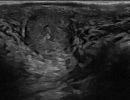

Πολλές αλλοιώσεις και παθήσεις μπορούν να απεικονιστούν υπερηχογραφικά και να μελετηθούν αξιόπιστα με τη βοήθεια του Έγχρωμου Doppler και της Ελαστογραφίας .

- Όγκοι των σιελογόνων αδένων ή της γλώσσας